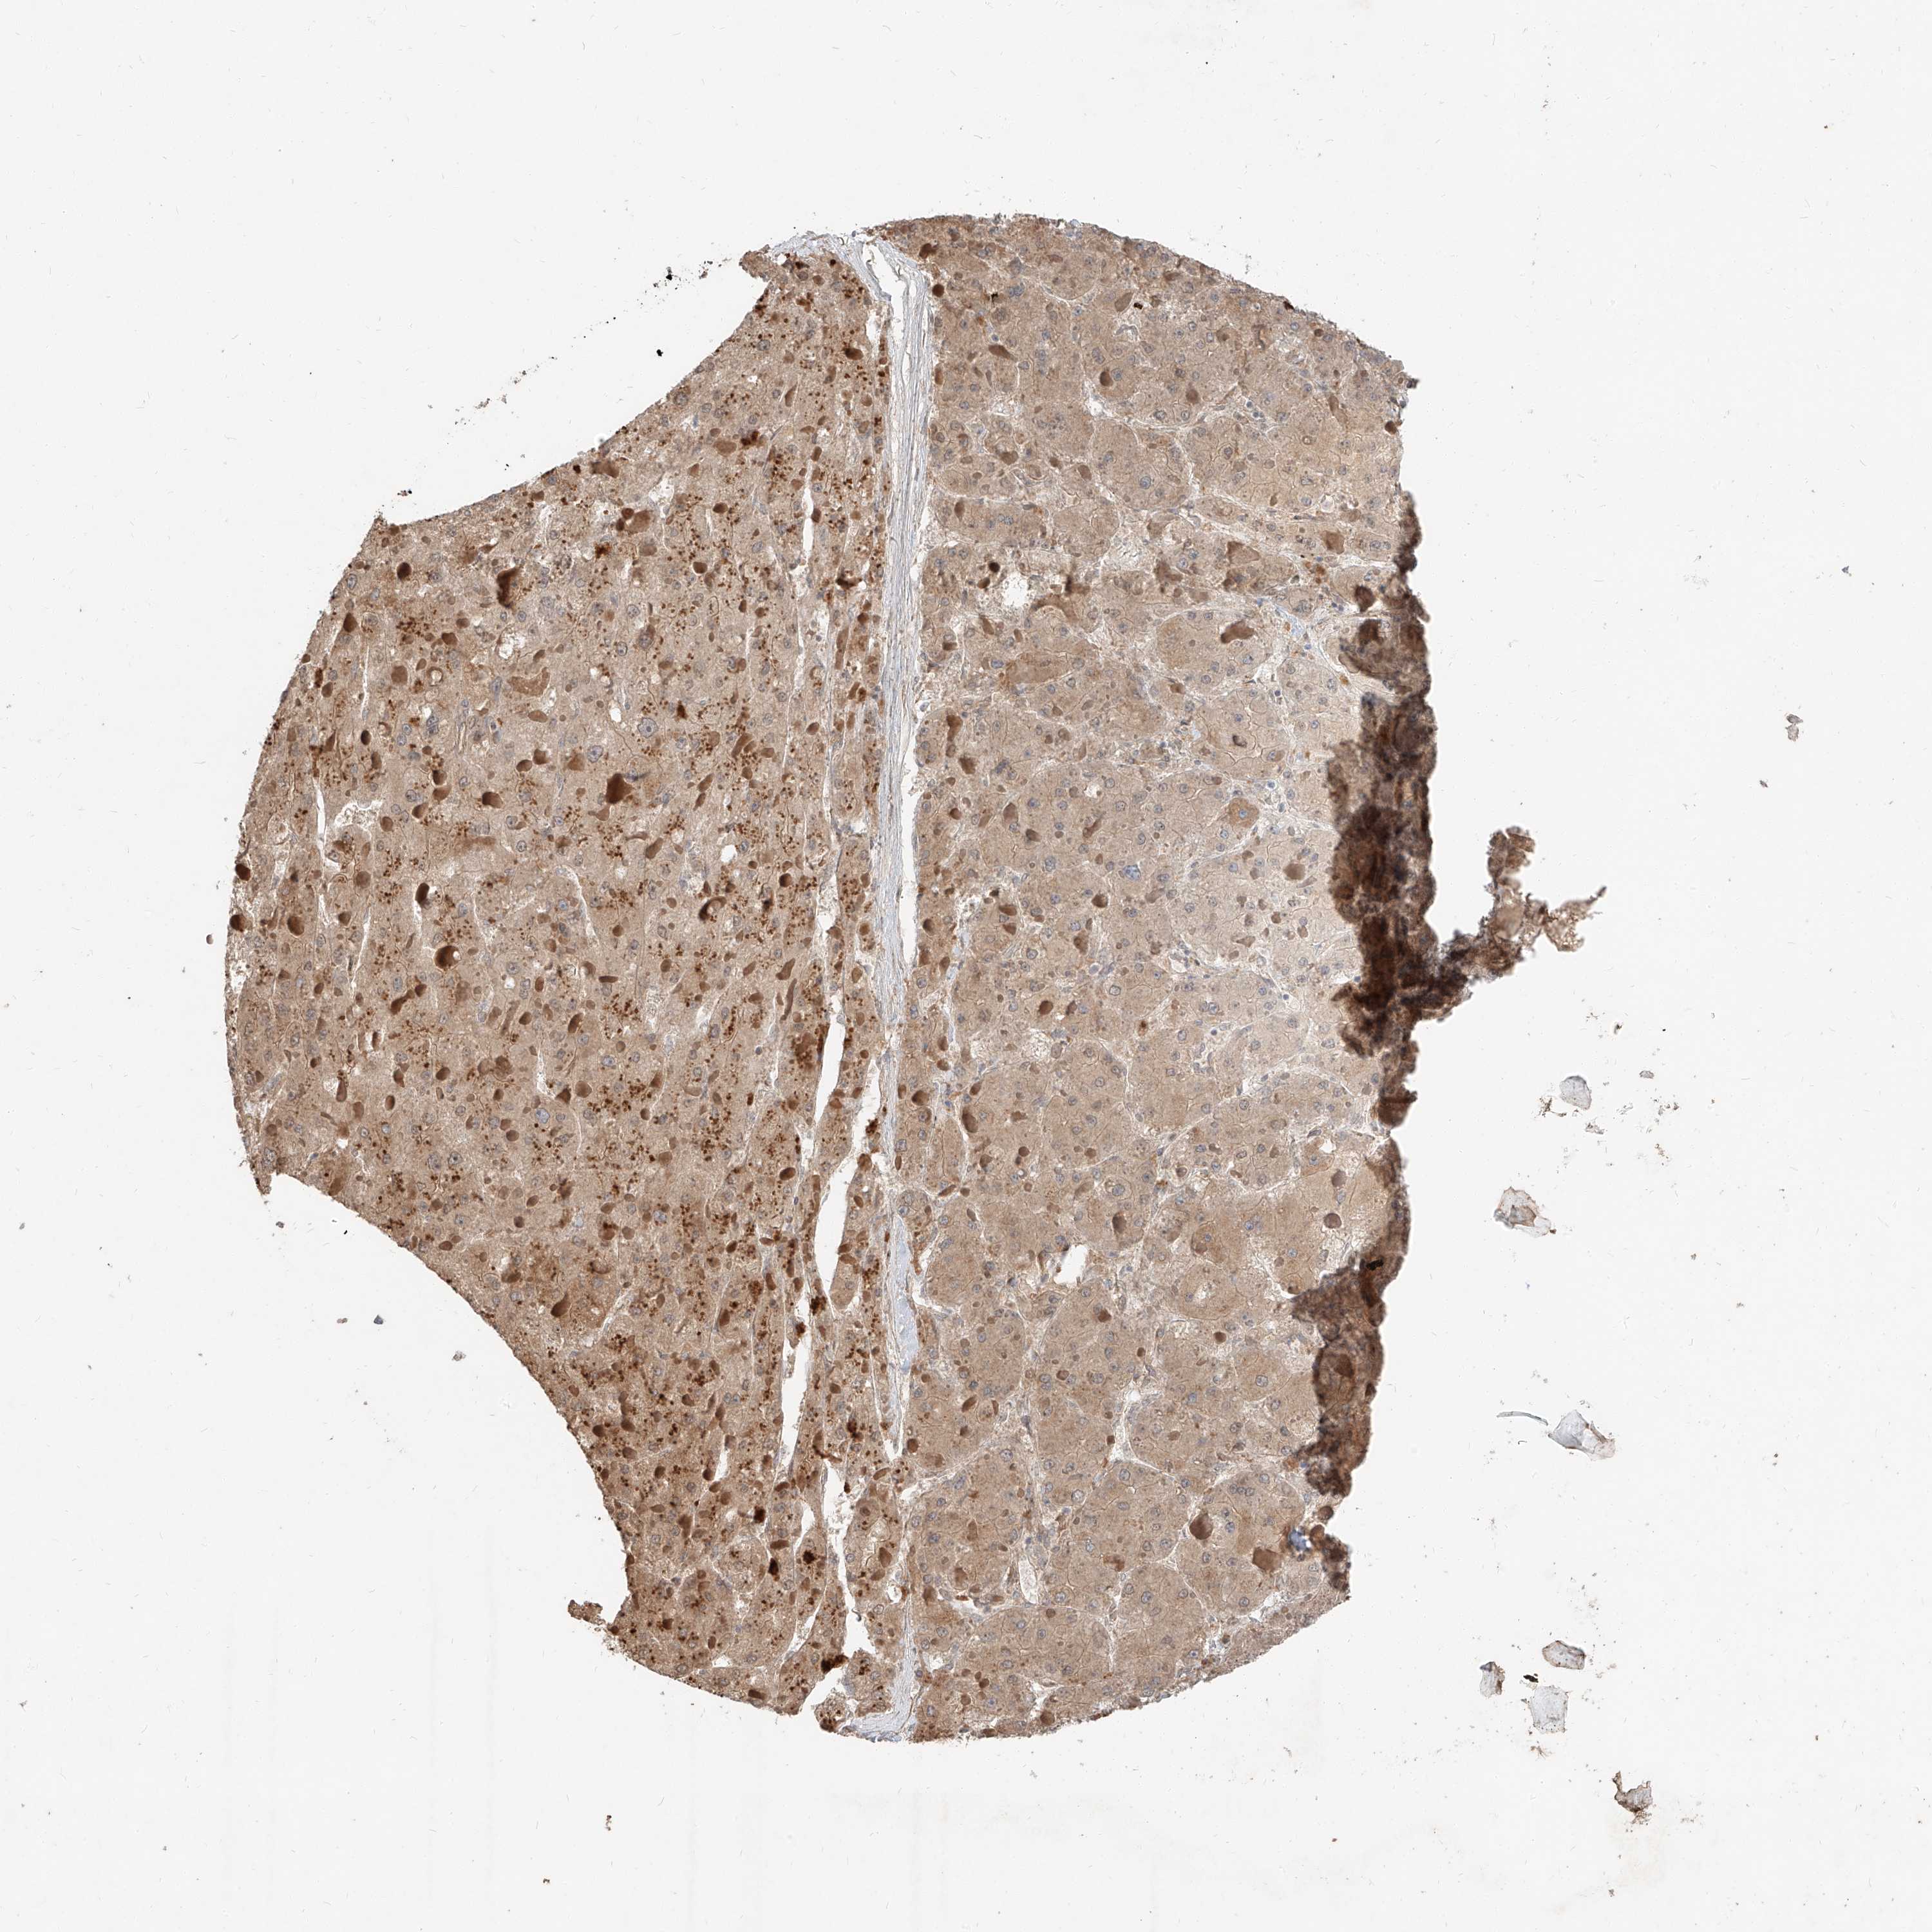

LIVER CANCER - Protein expressioni

A mouse-over function shows sample information and annotation data. Click on an image to view it in a full screen mode. Samples can be filtered based on level of antibody staining by selecting one or several of the following categories: high, medium, low and not detected. The assay and annotation is described here.

Note that samples used for immunohistochemistry by the Human Protein Atlas do not correspond to samples in the TCGA dataset.

Antibody stainingi

Antibody staining in the annotated cell types in the current human tissue is reported as not detected, low, medium, or high, based on conventional immunohistochemistry profiling in selected tissues. This score is based on the combination of the staining intensity and fraction of stained cells.

Each image is clickable and will lead to virtual microscopy that enables deeper exploration of all samples and also displays staining intensity scores, fraction scores and subcellular localization as well as patient and tissue information for each sample.

Antibody HPA030604

Staining

High

Medium

Low

Not detected

Intensity

Strong

Moderate

Weak

Negative

Quantity

>75%

75%-25%

<25%

None

Location

Nuclear

Cytoplasmic/membranous

Cytoplasmic/membranous,nuclear

Cholangiocarcinoma

Carcinoma, Hepatocellular, NOS